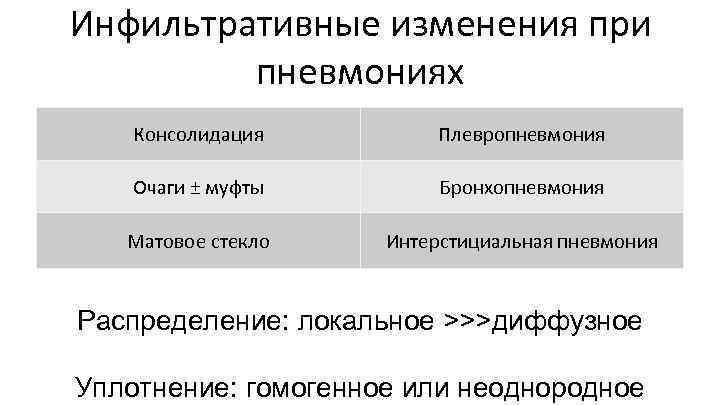

Инфильтративные изменения при пневмониях Консолидация Плевропневмония Очаги ± муфты Бронхопневмония Матовое стекло Интерстициальная пневмония Распределение: локальное >>>диффузное Уплотнение: гомогенное или неоднородное